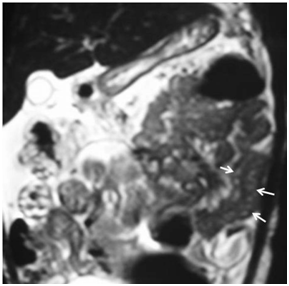

Four patients were included and their clinical characteristics are detailed in Table 2. The mean age of symptomatic presentation was 44.25 months (1‒109 months) while mean interval between onset of symptoms to diagnosis was 15.5 months (3‒26 months). The main presenting complaint was chronic diarrhea in 3 of 4, while 1 had presented with repeated episodes of generalized edema. All had features of protein losing enteropathy, high fecal fat, lymphangiectasia on biopsy and no underlying etiology for the IL could be identified. The imaging findings were of diffuse bowel thickening, tubular hyper‒intense channels within the sub‒serosal layer of the small bowel (Figure 1). One patient showed segmental localization, with limited involvement of the jejunum (Figure 2a & 2b).

Figure 2 MR images of a 11 month female child with intestinal lymphangiectaisa. Coronal HASTE (a) and axial T2W spin echo fat saturated (b) images show ascites and diffuse thickening of the mid and distal jejunal and ileal loops. There are multiple tubular and tortuous hyperintense channels in the jejunum (arrow); note the normal thickness of the proximal jejunal walls (block arrow).

In our study of 4 children with PIL, which is a rather rare disease with approximately 200 cases reported; we have find MRI to be accurate in diagnosis and segmental localization. We found findings on MRI to be bowel wall thickening, bowel wall enhancement and intramural hyper‒intensities in the affected bowel wall (Figure 1 & 2). All the 4 patients had bowel wall thickening and 3 of the 4 had intramural linear hyper‒intense signal intensity on T2WI MRI (Figure 1 & 2). One patient demonstrated localized involvement of the distal jejunal loops only on imaging (Figure 2). The sensitivity of MRI to detect lymphangiectasia on the basis of bowel wall thickening is 100% (taking endoscopy and biopsy as gold standard) while it was 75% if the finding of T2WI hyperintense linear signal intensity in the bowel wall was taken as a diagnostic criteria. Specificity could not be calculated as there was no ‘true negative’.